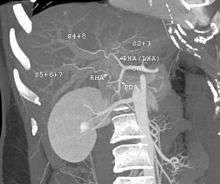

-

MDCT image. Arterial anatomy contraindicated for liver donation